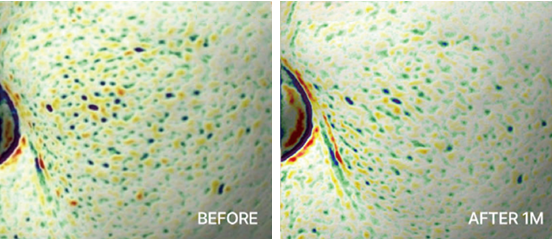

Elasticity Enhancement

Elasticity Enhancement